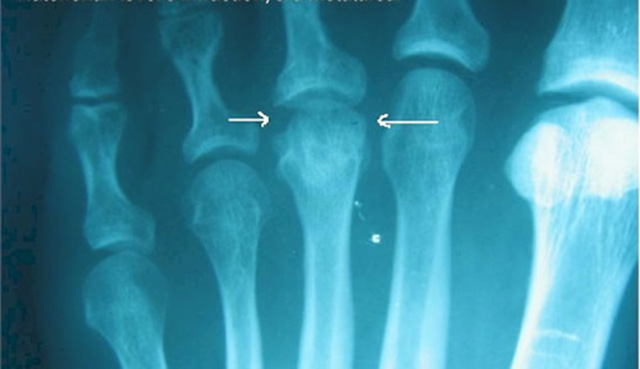

Σε αυτή τη μορφή οστεοχόνδρωσης παρουσιάζεται μια ανώμαλη ευθυγράμμιση στην δεύτερη μεταταρσιαία κεφαλή σε σχήμα “τρομπέτας”. Πρέπει να σημειωθεί ότι, μιας και η διαδικασία δημιουργίας είναι σταδιακή, οι πρόωρες ακτινογραφίες μπορεί να μην εμφανίσουν αυτά τα σημάδια. Αυτή η μορφή οστεοχόνδρωσης συσχετίζεται με τις παρακάτω δυσλειτουργίες και παθήσεις του άκρου ποδός: